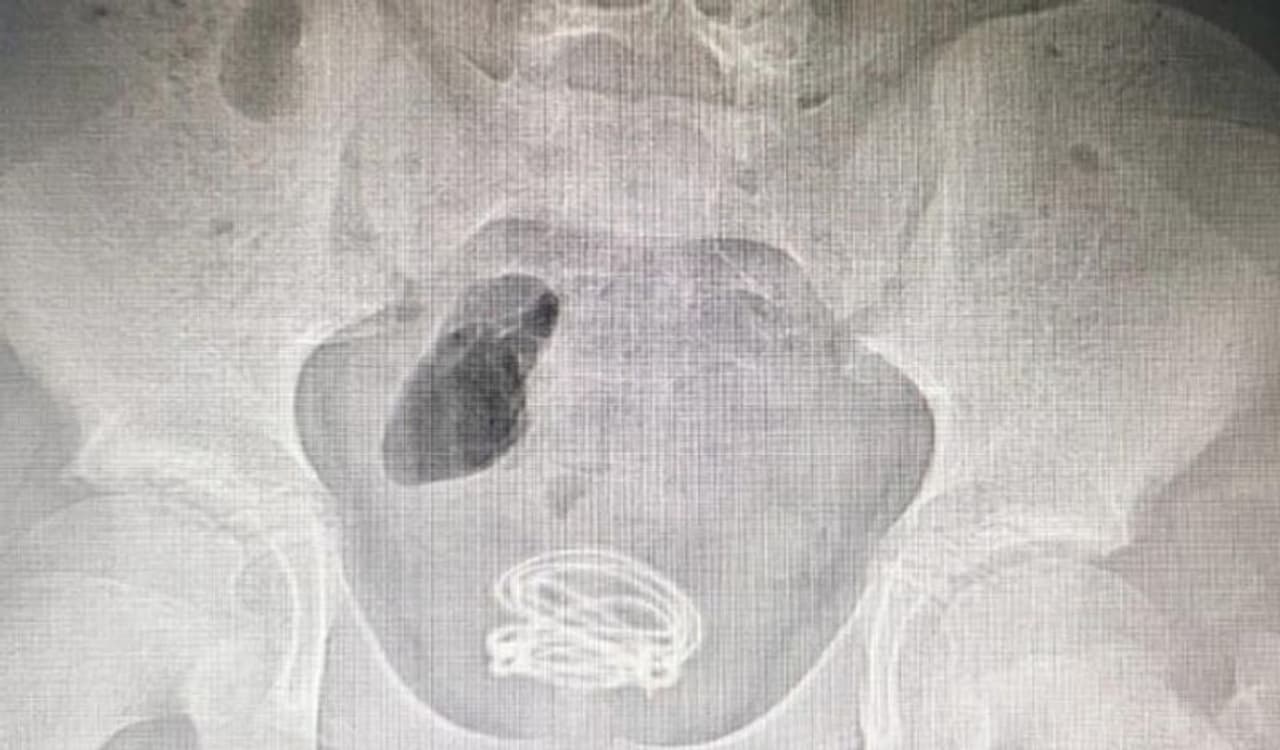

जब बच्चे की एक्सरे रिपोर्ट आई, तो सब हैरान रह गए। उन्होंने देखा कि बच्चे के ब्लेडर में दो फुट लंबी तार है। इसके तुरंत बाद बच्चे को एडमिट कर लिया गया।

डॉक्टर्स ने सर्जरी कर बच्चे के मूत्राशय से दो फुट की तार बाहर निकाली। जब बच्चे से इसके बारे में पूछा गया तो उसने बताया कि तीन महीने पहले उसने इस तार को प्राइवेट पार्ट के जरिये बॉडी में घुसाया था।

डॉक्टर्स ने सर्जरी के बाद बच्चे की जान बचा ली। उन्होंने कहा कि गनीमत है कि तार से बच्चे को कोई नुकसान नहीं पहुंचा। इस सर्जरी में घंटे का समय लगा। जिसके बाद 70 सेंटीमीटर लंबा तार बाहर निकाला गया।